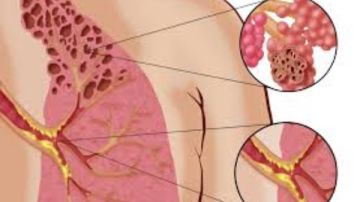

تصاعدت مؤخرًا التحذيرات الطبية العالمية من مرض تنفسي نادر وخطير يُعرف باسم 'رئة الفشار' (Popcorn Lung)، وهو الاسم الشائع لمرض التهاب القصيبات المسدّ.

يؤدي مرض رئة الفشار إلى تلف دائم في الرئتين ويُسبب مشكلات تنفسية مزمنة قد تُؤثر بشكل كبير على جودة حياة المصابين، وفقا لما نشر في موقع “مايو كلينك” الطبي.

ورغم أن الاسم قد يبدو غريبًا أو حتى طريفًا للبعض، فإن 'رئة الفشار' تُعد من الحالات التنفسية الخطيرة التي لا يمكن علاجها بشكل نهائي.

مرض رىة الفشار يتمثل في التهاب القصيبات المسدّ، وهو حالة تُصيب الشعب الهوائية الدقيقة داخل الرئتين، مما يؤدي إلى تندّبها تدريجيًا وانسدادها، وبالتالي تقييد تدفق الهواء وإعاقة عملية التنفس.